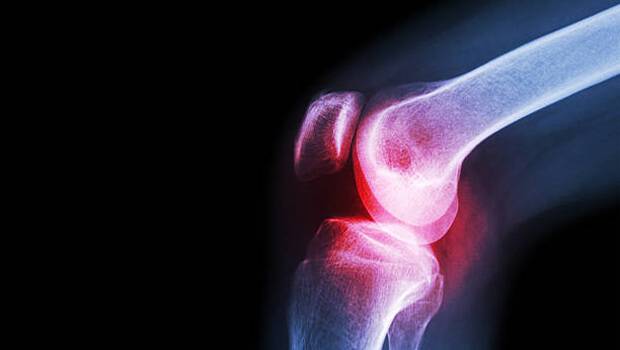

تستهای تصویربرداری

عکسبرداری با اشعه ایکس و دیگر آزمایشات تصویربرداری از مفصل آسیبدیده میتواند وضعیت مفصل را نشان دهد.